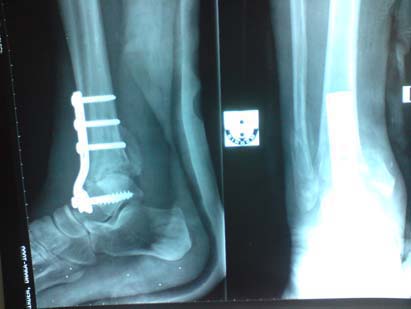

X-rays of the ankle and foot were done in BIRDEM and revealed gross osteopenia, soft tissue swelling and fracture-dislocation of the left ankle with bony fragmentation and callus formation at the fracture site (Fig.3). His inflammatory markers of the blood were unremarkable. The clinical picture and investigations were considered compatible with a Charcot arthropathy of left ankle. Arthrodesis of the ankle was done with a ‘T’ shaped plate and five screws and immobilised with a short leg plaster cast. His ankle fused over the next twelve months.

Fig. 3. Pre-operative X-ray:Fracture and dislocation in a left ankle Charcot joint

Fig. 4. Post-operative X-ray: Ankle arthrodesis with plate and screws